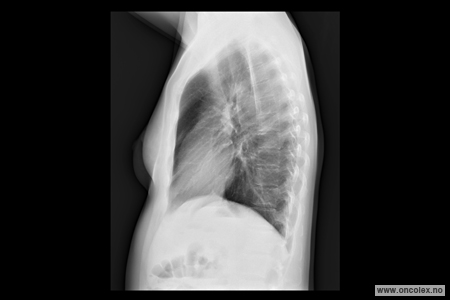

Røntgen toraks er en røntgenundersøkelse som tas for å se på lunger, hjerte og lymfeknuter i brystskilleveggen mellom lungene.

Du blir bedt om å kle av deg på overkroppen og stå foran et røntgenapparat. Deretter vil du få beskjed om å trekke pusten dypt inn og holde pusten når bildene blir tatt. Det tas front- og sidebilde. I spesielle tilfeller, for eksempel dersom du ikke klarer å stå oppreist, kan bildene tas mens du sitter eller ligger i sengen.